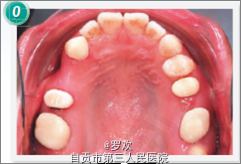

闭唇时颏肌紧张,露龈笑,凸面型 A4A6B6 缺失,A3-A7,B5-7 局部固定桥修复 II类关系(右侧) ,下中线右偏2mm 侧位片:高角,凸面型,唇前突, SNA82°,SNB78°,ANB4°, 全景:多个牙缺失

诊断:牙列缺损,凸面型,露龈笑 处理:上颌:内收上颌前牙,关闭磨牙缺失间隙,垂直向压低整个上颌牙列 下颌:内收下颌切牙,从而内收前突的唇。 拔除双侧下颌4,去除上颌局部固定桥,制作基牙的临时冠,,在上颌右侧3和5之间保留7.5mm的间隙供种植修复4,关闭所有间隙,种植钉内收和压低上颌前牙段,种植钉打在 颧牙槽嵴上,从种植钉上伸出悬臂簧用于压入上前牙以改善露龈笑,矫正结束后,在上下颌前牙段粘接舌侧丝固定保持